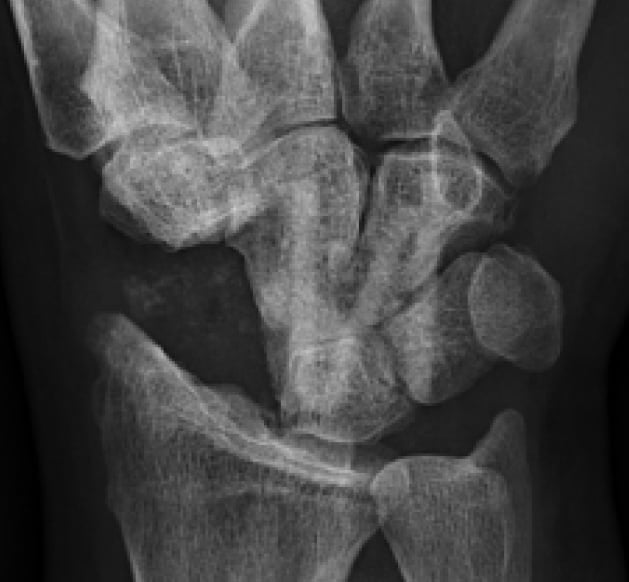

4 Tage postoperativ

Röntgenbildkontrolle nach Resektion des Scaphoids und Four-Corner-Fusion mit 3 Knochenschrauben-Transplantaten.